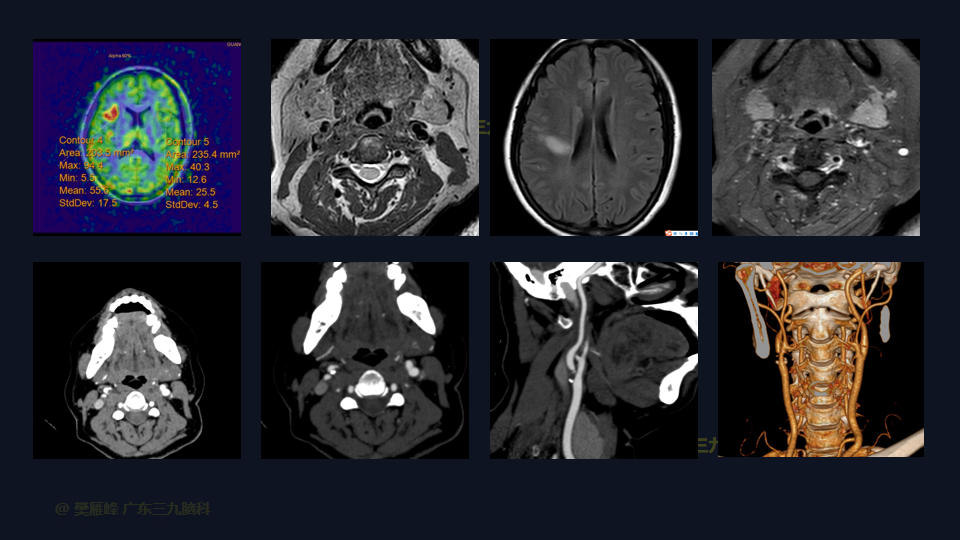

在这个二维手术视频中,展示了颈动脉内膜剥脱术(carotid endarterectomy,CEA)治疗严重的颈动脉动脉狭窄。患者是一名59岁的女性,有发作性言语不清、口角歪斜1周入院,MR血管高分辨平扫+增强+灌注成像示:1.右侧颈内动脉起始部管腔重度狭窄-接近闭塞,伴粥样硬化改变合并管壁斑块形成,并管壁轻度炎性改变;ASL检查右侧额颞顶叶及右侧基底节区多发低灌注影提示缺血改变,局部皮层区为主间杂多发高灌注影提示慢血流改变可能。经颅彩色多普勒血流图(TCD):左侧大脑中动脉中度狭窄,右侧颈内动脉虹吸段轻度狭窄。他接受了颈动脉内膜剥脱手术,手术顺利,术中造影显示血管通畅。术后一般情况尚可,无新发神经功能障碍,神经影像学显示血管通畅。术后继续康复治疗。术后3月复查DSA显示血管通畅。左侧鼻唇沟稍浅,左上肢肌力IV级、左下肢肌力V级-,右侧肢肢体肌力V级。我们展示了颈动脉的分离、斑块切除和颈动脉缝合的细微差别和技术要点。